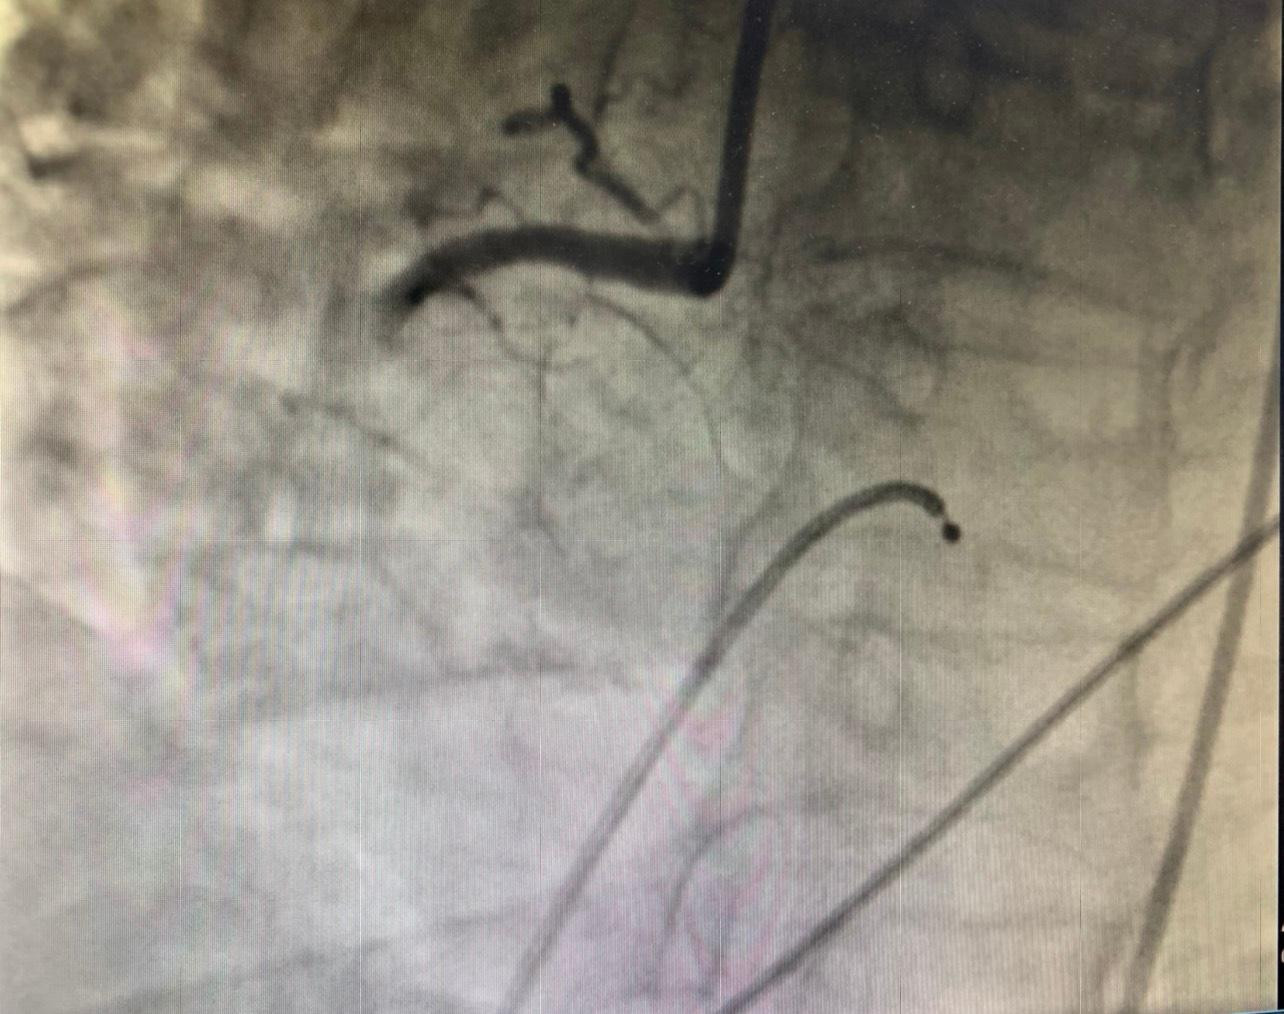

| Mạch vành của bệnh nhân (hình trên) bị tắc nghẽn trước can thiệp và được tái thông sau can thiệp (hình dưới) |

Tại Bệnh viện Thống Nhất, trong vòng 5 phút thăm khám, đo điện tim, các bác sĩ đã phát hiện bệnh nhân bị nhồi máu cơ tim cấp ở vị trí thành dưới, thất phải và thành sau thất trái khiến huyết áp của bệnh nhân tụt, mạch chậm dần.

Người bệnh nhanh chóng được chỉ định can thiệp nội mạch để tái thông vị trí mạch máu bị tắc nghẽn. Tuy nhiên, khi chuyển đến phòng DSA, bệnh nhân bất ngờ bị rung thất, nguy cơ tử vong ngay lập tức. Các bác sĩ đã nỗ lực sốc điện, hồi sinh tim phổi nhiều lần.

Thế nhưng, tình trạng rung thất của người bệnh vẫn lặp đi lặp lại. “Nếu chờ cho bệnh nhân ổn định mới can thiệp thì chúng tôi không có cơ hội. Với quyết tâm cứu bệnh nhân, ê kíp liên chuyên khoa đã quyết định vừa sốc điện chuyển nhịp để xử lý tình trạng rung thất đồng thời vừa can thiệp đặt stent cho bệnh nhân. Sau hơn 5 phút chạy đua với tử thần, tổng cộng hơn 30 lần sốc điện, chúng tôi đã can thiệp thành công mạch vành, đặt 1 stent tái thông vị trí mạch máu bị tắc tạm thời giúp người bệnh qua được nguy kịch” – PGS.BS Nguyễn Văn Tân cho hay.

Theo PGS.BS Nguyễn Văn Tân, thực tế can thiệp mạch vành cho thấy, bệnh nhân tổn thương cả 2 nhánh, trong đó nhánh bên phải tắc hoàn toàn đoạn gần (RCA) do huyết khối. Tuy nhiên, sau can thiệp, bệnh nhân tiếp tục bị nhịp nhanh thất, rung thất. Các bác sĩ đã tiếp tục sốc điện, đồng thời sử dụng thuốc, bổ sung điện giải giúp bệnh nhân phục hồi dần.